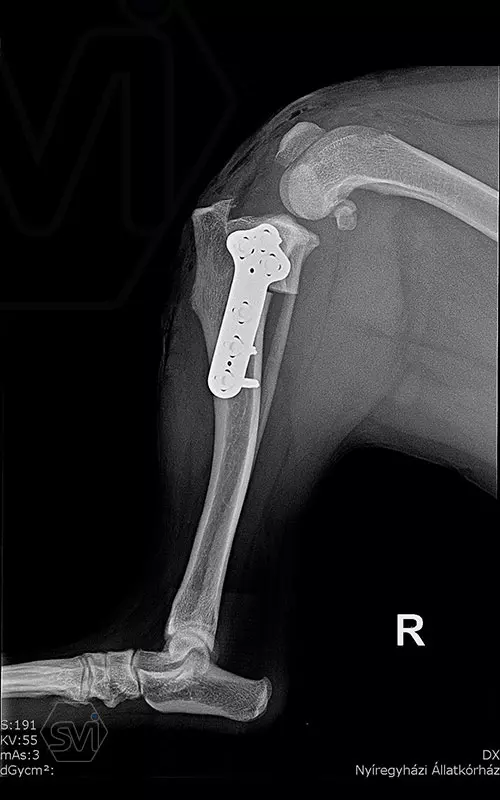

1,5 year old 13 kg mix dog underwent surgery today due to cranial cruciate ligament rupture and concomitant grade 3/4 medial patella luxation. During surgery, lateral tightening and medial loosening of the joint capsule (without opening the capsule) was performed. In the first phase of surgery, the 26-degree TPA was corrected simultaneously with the medial transposition of the proximal fragment. An R18 TPLO blade was used and the step and the rotation was fixed with a 2.7 precontured TPLO plate. The big curvature of the precontured plate provided an opportunity for placement without further conuring of the plate. The plate was temporarily fixed to the bone surface with two 1.2 K-nails using holes for temporary fixation. The distal piece was first stabilized with two locking screws. An AO 2,7mm srew was placed in the cranial hole of the proximal piece, which was able to create a significant tuberositas tibiae shift by tightening and simultaneously removing the temporaly, rotation stabilizing K-wire. Polyaxial locking screws are inserted into the remaining holes.

Thus, during surgery, we successfully applied a member of the precontured plate family designed for 2.7 mm screws for TPLO-M surgery.